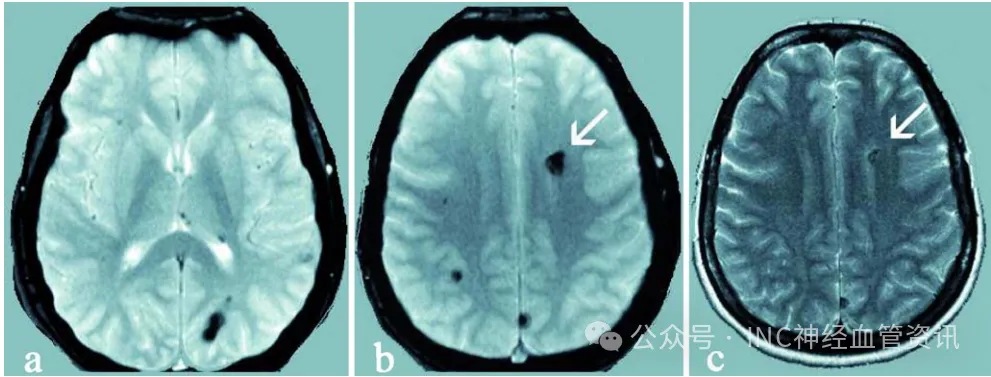

艾米娜在急性出血及神经功能恶化后1个月,出现嗜睡、头痛、右侧偏瘫伴面瘫以及言语障碍。而最近这一次突然加重是由于先前诊断的桥脑海绵状血管瘤增大并出血,伴有轻度脑积水。

复查MRI显示左侧桥脑海绵状血管瘤,最大尺寸为4×3.5×3厘米(图1)。同时在大脑其他部位也发现了多个类似病灶。